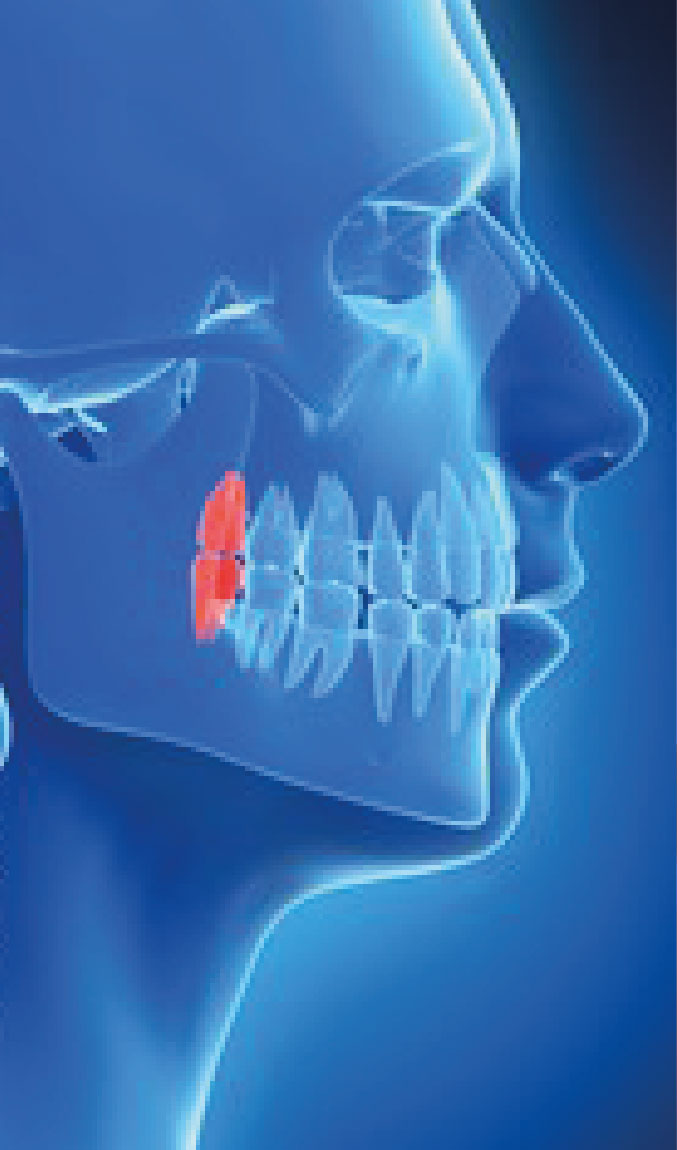

L’avulsion des dents de sagesse : Elle peut être réalisée préventivement lorsque votre Dentiste ou votre Orthodontiste constate qu’il manque de la place dans votre mâchoire, ou bien plus tardivement en raison d’une complication infectieuse.

Voir la fiche d’information : ![]() Avulsion Dents de Sagesse –